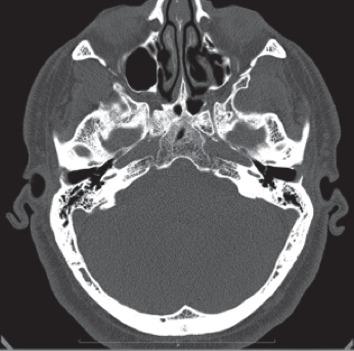

is a bacterium belonging to the family . It is a rare but emergent cause of human pathologies especially in immunocompromised patients. We described the first case in the literature of isolated external otitis sustained by in an immunocompetent host. A 54-year-old Caucasian man with a history of previous myringoplasty came to our attention reporting otalgia and otorrhea. We performed right ear swab for culture examination, meanwhile we started empirical therapy with topic administration of neomycin, without any clinical improvement. The cultural examination showed the presence of a infection. After ten days of treatment with oral ciprofloxacin and topic levofloxacin, there was the complete resolution of pain and inflammation. must be taken into consideration as an emergent cause of human infection, also in case of external otitis. Infection can be severe and can occur both in immunocompromised and in immunocompetent hosts. Culture test is mandatory to choose the proper therapy and avoid potential severe complications.

是一种属于 科的细菌。它是人类疾病的一种罕见但新兴的病因,尤其是在免疫功能低下的患者中。我们描述了文献中首例由 在免疫功能正常宿主中引起的孤立性外耳炎病例。一名有鼓膜成形术史的54岁白种男性因耳痛和耳漏前来就诊。我们进行了右耳拭子培养检查,同时开始局部应用新霉素进行经验性治疗,但无任何临床改善。培养检查显示存在 感染。在用口服环丙沙星和局部用左氧氟沙星治疗十天后,疼痛和炎症完全消退。 必须被视为人类感染的一种新兴病因,即使在外耳炎的情况下也是如此。感染可能很严重,并且可发生在免疫功能低下和免疫功能正常的宿主中。培养测试对于选择合适的治疗方法和避免潜在的严重并发症是必不可少的。